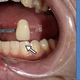

歯の色をAIが判定するシステムの効果

明星大学情報学部の植木一也准教授らは、人工知能(AI)を活用し、義歯製作で本来の歯の色調を再現するための色判定システムの開発を始めた。人手…